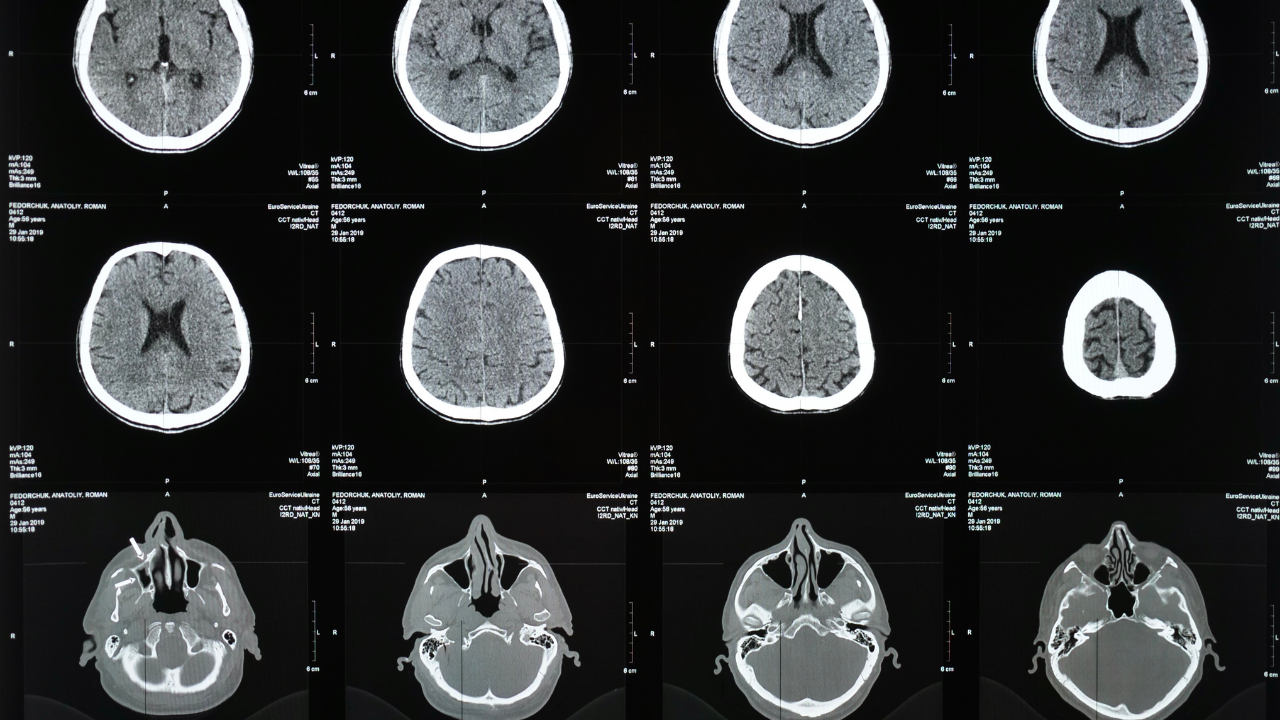

Modern nörobilim, bilinci genellikle beyinle özdeşleştirir.

MR cihazları, EEG dalgaları, nöronların elektriksel sinyalleri…

Evet, bilinçli bir deneyim sırasında beyin bölgeleri aktif hale gelir.